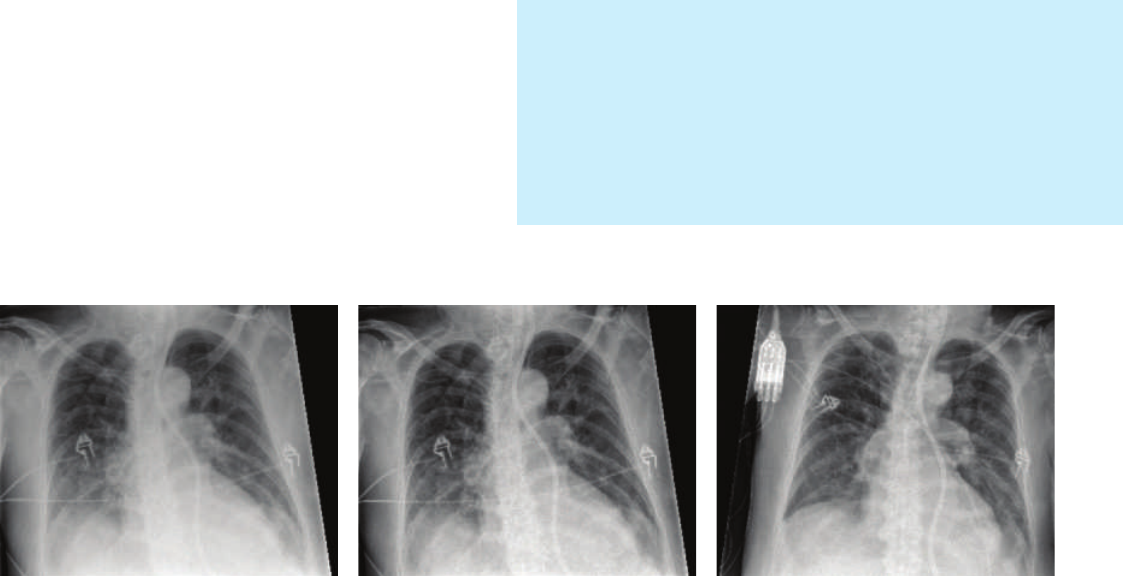

Naturally, the clinician always decides whether or not to use a grid. When working without a grid, SkyFlow

portable thorax X-rays provides grid-like image contrast without actually using one. By combining the large

SkyPlate with SkyFlow, your facility will be able to work quickly and conveniently by avoiding the time and effort

of attaching and detaching a grid.

Reference image acquired without grid Same exposure, now processed with SkyFlow Image of same patient acquired on a different day.

A grid was used, and X-ray dose was increased by a

factor of 1.6

* SkyFlow is available with DigitalDiagnost 4.0 and 4.1 and MobileDiagnost wDR 2.0